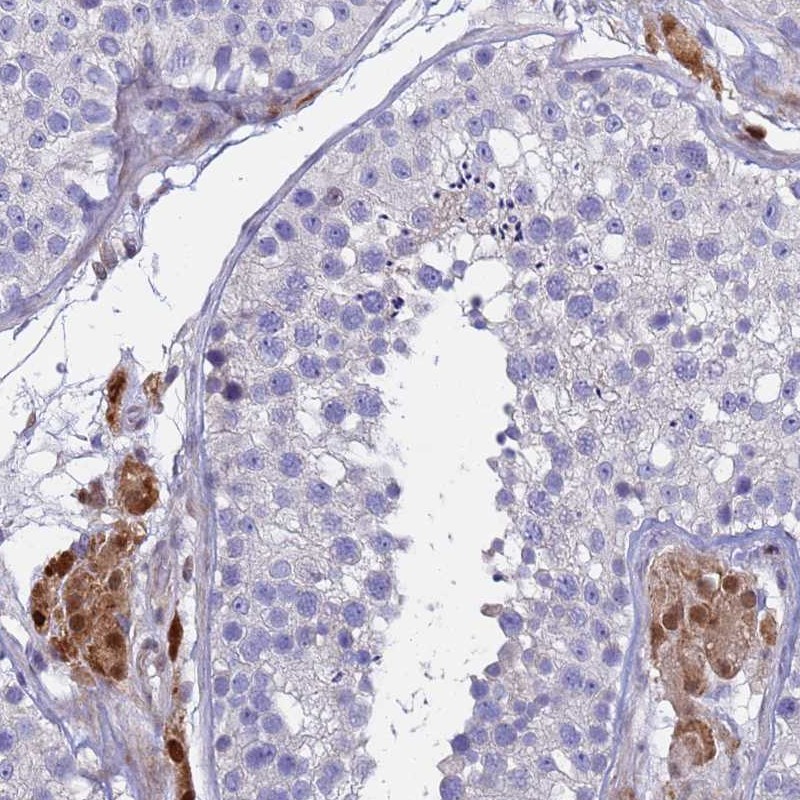

Immunohistochemical staining of human testis shows strong nuclear and cytoplasmic positivity in Leydig cells.